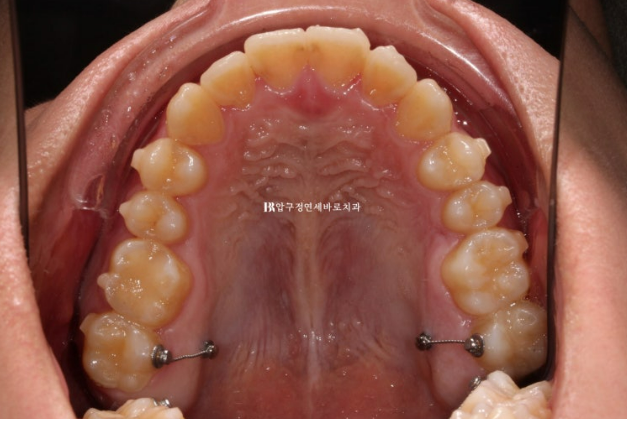

주걱턱 (3급 부정교합)에서는 상악 맨 뒤 큰 어금니가 대합치가 없어 내려와 있는 경우가 많습니다.

이 부분 해결을 위해 입천장에 교정용 나사 미니스크류를 심고 술전교정을 진행했습니다.

약 4개월의 술전교정 후 모습입니다.

23.12

내려와있던 위 맨 뒤 큰 어금니는 제 위치로 잘 올라갔고 양악수술을 위해서 철사로 고정을 해둡니다.